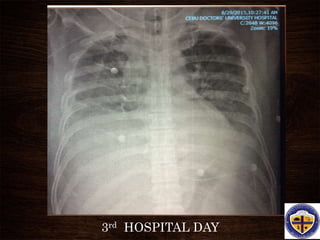

3rd HOSPITAL DAY